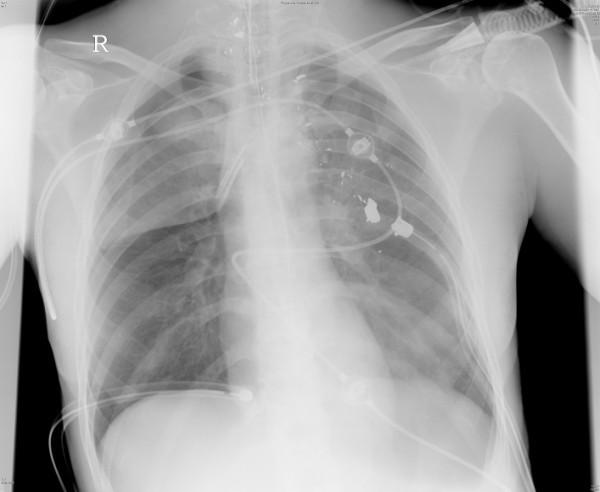

Craniocerebral gunshot injuries are often lethal, especially after suicide attempts. The treatment of non space consuming haematomas and the indications for invasive pressure measurement are controversial. Civilian gunshot injuries to the torso mostly intend to kill; however for those patients who do not die at the scene and are hemodynamically stable, insertion of a chest tube is usually the only required procedure for the majority of penetrating chest injuries. In penetrating abdominal injuries there is a trend towards non-operative care, provided that the patient is hemodynamically stable. Spinal gunshots can also often be treated without operation. Gunshot injuries of the extremities are rarely life-threatening but can be associated with severe morbidity.With the exception of craniocerebral, bowel, articular, or severe soft tissue injury, the use of antibiotics is controversial and may depend on the surgeon's preference.

The treatment strategy for patients with gunshot injuries to the torso mostly depends on the hemodynamic status of the patient. Whereas hemodynamically unstable patients require immediate operative measures like thoracotomy or laparotomy, hemodynamically stable patients might be treated with minor surgical procedures (e.g. chest tube) or even conservatively.

颅脑枪伤通常是致命的,尤其是在自杀未遂后。对于非占位性血肿的治疗以及有创压力测量的指征存在争议。平民躯干枪伤大多意图致死;然而,对于那些没有在现场死亡且血流动力学稳定的患者,对于大多数穿透性胸部损伤而言,插入胸管通常是唯一所需的操作。对于穿透性腹部损伤,如果患者血流动力学稳定,则有采用非手术治疗的趋势。脊柱枪伤通常也可以不通过手术进行治疗。四肢枪伤很少危及生命,但可能伴有严重的发病率。除了颅脑、肠道、关节或严重软组织损伤外,抗生素的使用存在争议,可能取决于外科医生的偏好。

躯干枪伤患者的治疗策略主要取决于患者的血流动力学状态。血流动力学不稳定的患者需要立即采取手术措施,如开胸手术或剖腹手术,而血流动力学稳定的患者可能采用小型外科手术(如胸管插入)甚至保守治疗。